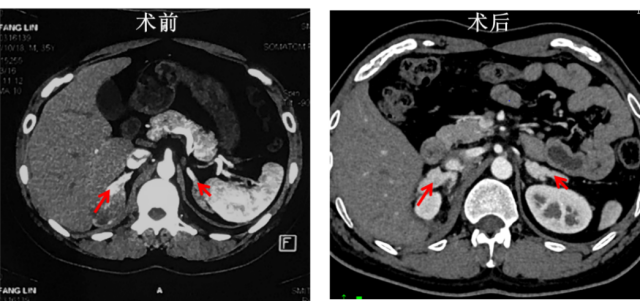

在随后复查过程中,南方医院内分泌科医生发现,李先生对侧和术后残留的肾上腺组织在10天之内出现了明显增粗。这引起了团队成员的高度重视,因肾上腺皮质癌本身无法解释这一临床发现,结合李先生描述的性发育早且雄激素分泌旺盛等表现,考虑他可能同时患有肾上腺皮质增生症(CAH)的可能。

李先生术后残留的肾上腺组织出现明显增粗。 受访者供图